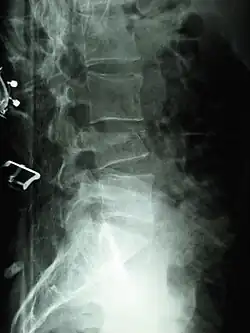

A compression fracture is a collapse of a vertebra. It may be due to trauma or due to a weakening of the vertebra (compare with burst fracture). This weakening is seen in patients with osteoporosis or osteogenesis imperfecta, lytic lesions from metastatic or primary tumors,[1] or infection.[2] In healthy patients, it is most often seen in individuals suffering extreme vertical shocks, such as ejecting from an ejection seat. Seen in lateral views in plain x-ray films, compression fractures of the spine characteristically appear as wedge deformities, with greater loss of height anteriorly than posteriorly and intact pedicles in the anteroposterior view.[3]

Compression fractures are usually diagnosed on spinal radiographs, where a wedge-shaped vertebra may be visible or there may be loss of height of the vertebra. In addition, bone density measurement may be performed to evaluate for osteoporosis. When a tumor is suspected as the underlying cause, or the fracture was caused by severe trauma, CT or MRI scans may be performed.

Compression fracture of T12